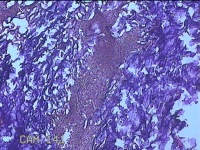

右侧颜面部结节

性别

男

年龄

35岁

临床诊断

皮脂腺囊肿

一般病史

发现右侧颜面部结节9个月余,无明显疼痛及不适。

标本名称

大体所见

灰白暗红色带皮肤样结节3x2x0.8cm一堆,表面糜烂。